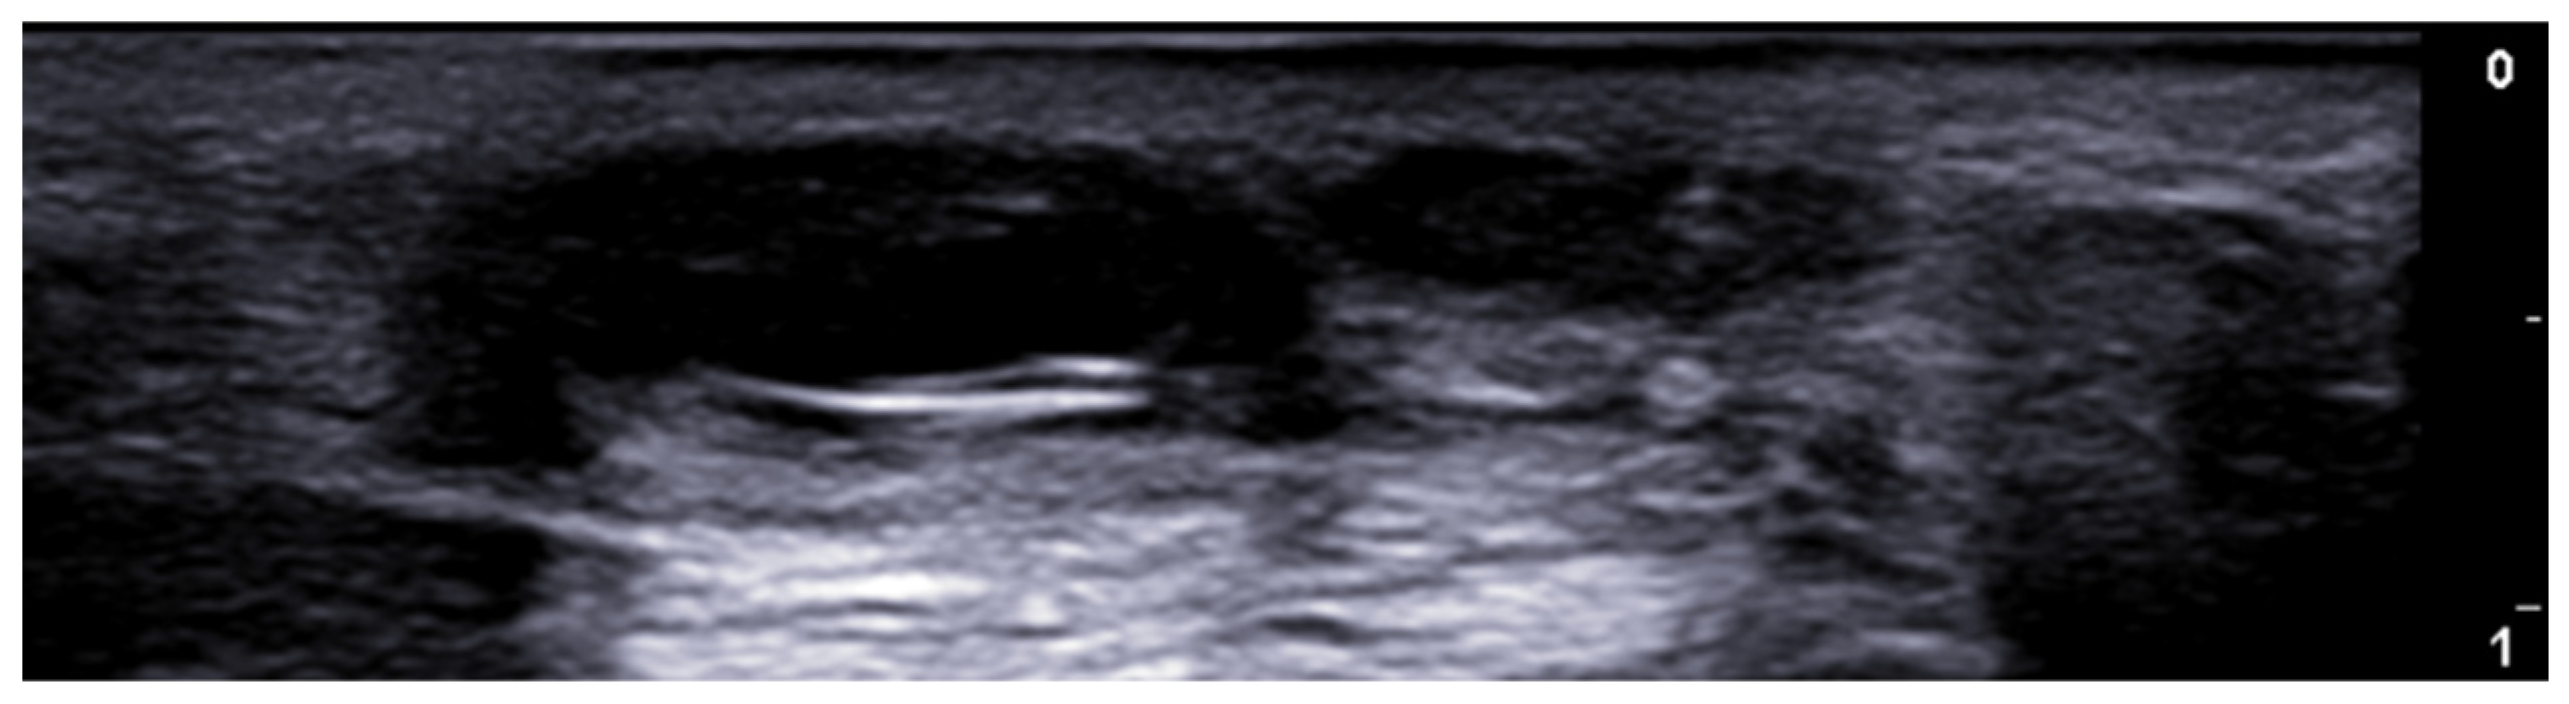

- Dini, V.; Michelucci, A.; Granieri, G.; Zerbinati, N.; Margiotta, F.M.; Romanelli, M. Evaluation of post-surgical complications of hidradenitis suppurativa lesions explored with presurgical ultra-high frequency ultrasound mapping. J. Wound Care 2024, 33, S10–S16. [Google Scholar] [CrossRef]

- Michelucci, A.; Fidanzi, C.; Manzo Margiotta, F.; Granieri, G.; Salvia, G.; Janowska, A.; Romanelli, M.; Dini, V. Presurgical Mapping with Ultra-high Frequency Ultrasound of Hidradenitis Suppurativa Lesions Treated with Wide Local Excision and Secondary Intention Healing. Dermatol. Surg. 2025, 51, 36–39. [Google Scholar] [CrossRef]